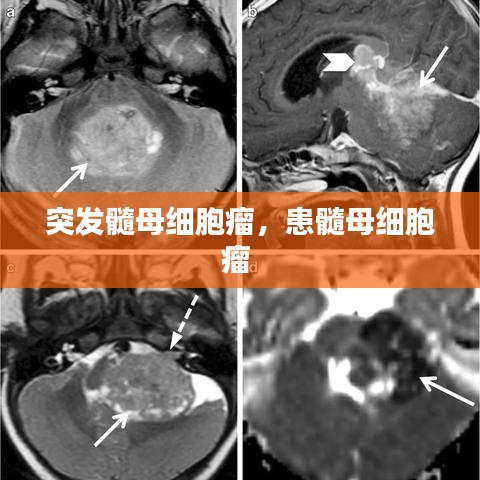

- 影像学检查:包括CT扫描、MRI和PET扫描,这些检查可以帮助医生确定肿瘤的位置、大小和性质。

突发髓母细胞瘤是一种严重的神经系统疾病,对患者的身心健康造成极大影响。早期诊断和综合治疗是提高患者生存率的关键。尽管目前没有特效的预防方法,但通过健康的生活方式和对环境的谨慎管理,我们可以降低患脑肿瘤的风险。对于疑似症状的患者,应及时就医,以便得到及时的诊断和治疗。